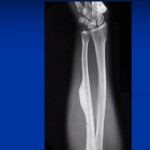

Osteopoikilosis

OSTEOPOIKILOSIS (OSTEOPATHIA CONDENSANS DISSEMINATE; SPOTTED BONES) Autosomal dominant inheritance, with loss of function mutation in…